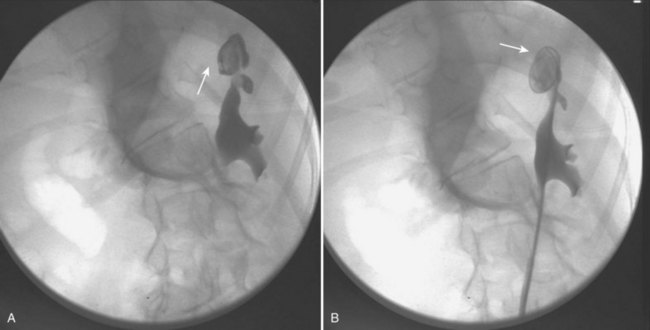

Standardization in the treatment of distal calculi in children has led a number of centers to expand ureteroscopy to the treatment of upper tract calculi (Table 135–2). Comparable stone-free rates approaching 100%, with complication rates similar to that of the adult population, have recently been reported (Minevich et al, 2005; Lesani and Palmer, 2006; Cannon et al, 2007; Corcoran et al, 2007; Smaldone et al, 2007). Smaldone and colleagues (2007) reported a 91% stone-free rate with a mean follow-up of 10 months in a series of 100 children with a mean stone diameter of 8.3 mm, 52% of whom had upper tract calculi. Nine percent of these children underwent staged procedures. They reported a 4.2% perforation rate that was managed with ureteral stenting and one distal ureteral stricture requiring open neocystostomy. Corcoran and colleagues (2007) reviewed a cohort of 47 children (mean age 9.4 years) with upper tract calculi managed with flexible ureteroscopy and holmium laser lithotripsy. An 88% stone-free rate with a mean stone burden of 10.2 mm was reported, with 26% requiring staged procedures. These authors concluded that because of improved ureteroscopic access to the pediatric upper tract, calculi up to 15 mm were as safely and effectively treated in children as in adults. Even with outstanding pediatric ureteroscopic technology, pediatric ureters may require a period of stenting prior to embarking on endoscopic treatment. For example, a smaller-caliber ureter that is resistant to instrumentation may be passively dilated with an indwelling stent during 6 to 8 weeks (Fig. 135–1).

Figure 135–1 CT scan (A) and retrograde pyelogram (B) in a 10-year-old female with glucose transport deficiency demonstrating a 9-mm renal pelvic stone (arrowheads). Nephrolithiasis was secondary to profound hypocitruria and hypercalciuria. Primary ureteroscopy could not be accomplished because of a narrowed segment of proximal ureter (arrow). Following 8 weeks of ureteral accommodation with an indwelling stent, flexible ureteroscopy with laser lithotripsy and stone basketing was performed.